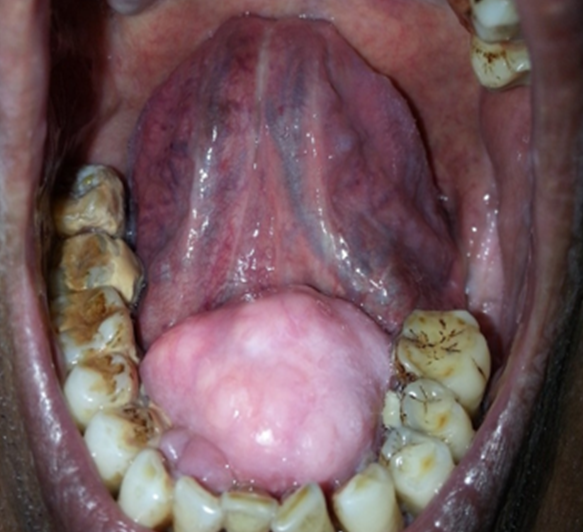

Torus mandibularis

A 54-year-old man who presented to the clinic for a routine examination was found to have a hard swelling in the floor of mouth. The swelling was noticed at the age of ten years and had been gradually progressing over the years. However, there was no history of chewing difficulty, dysphagia, dysarthria, oral ulcers or sleep disturbances. On examination, a 4x4 cm bony swelling was noted arising from the lingual surface of mandible, with an intact overlying mucosa. The findings were typical of torus mandibularis, a benign bony outgrowth from the mandible which was also confirmed radiologically. About 80 to 90% of the lesions present as small, bilateral bony protrusions near the pre-molars and are incidental findings on routine oral examination. Despite the large size, our patient declined any treatment as the lesion was asymptomatic.